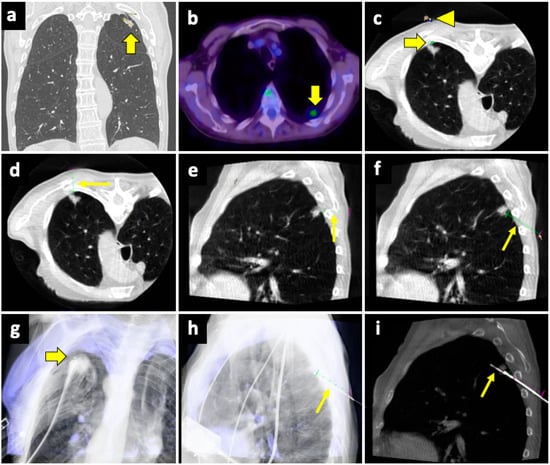

An example of a biopsy guided by fusion imaging between pre-procedural spectral CT and intra-procedural CBCT is illustrated in Figure 6.